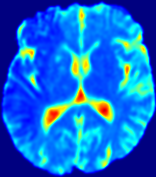

LesionRefer to captionRefer to captionRefer to captionRefer to captionRefer to captionRefer to caption𝐕rgbsubscript𝐕𝑟𝑔𝑏{\bf{V}}_{rgb}Refer to captionRefer to captionRefer to captionRefer to captionRefer to captionRefer to caption𝐕2subscriptnorm𝐕2{\|\bf{V}}\|_{2}Refer to captionRefer to captionRefer to captionRefer to captionRefer to captionRefer to captionRefer to caption3.53.53.52.82.82.82.12.12.11.41.41.40.70.70.70.00.00.0(mm/s)𝑚𝑚𝑠(mm/s)D𝐷DRefer to captionRefer to captionRefer to captionRefer to captionRefer to captionRefer to captionRefer to caption0.0200.0200.0200.0160.0160.0160.0120.0120.0120.0080.0080.0080.0040.0040.0040.0000.0000.000(mm2/s)𝑚superscript𝑚2𝑠(mm^{2}/s)Slice #1Slice #2Slice #3Slice #4Slice #5Slice #6

Figure 4: PIANO feature maps for another patient in the ISLES 2017 training set, where the lesion is located in the right hemisphere. Top row: segmented stroke lesion region (white) on different slices. The corresponding slices for the PIANO feature maps are shown in the following rows.

For a better insight into an estimated velocity field 𝐕𝐕{\bf{V}} and diffusion field 𝐃𝐃{\bf{D}}, we compute the following maps: (1) 𝐕rgbsubscript𝐕𝑟𝑔𝑏{\bf{V}}_{rgb}: Color-coded orientation map of 𝐕=(Vx,Vy,Vz)T𝐕superscriptsuperscript𝑉𝑥superscript𝑉𝑦superscript𝑉𝑧𝑇{\bf{V}}=(V^{x},V^{y},V^{z})^{T}, obtained by normalizing 𝐕𝐕{\bf{V}} to unit length and mapping its 3 components to red, green, blue respectively; (2) 𝐕2subscriptnorm𝐕2\|{\bf{V}}\|_{2}: 222 norm of 𝐕𝐕{\bf{V}}; (3) D𝐷D: scalar field in Eq. 5.

Fig. 3 and Fig. 4 show the PIANO feature maps estimated from two ISLES 2017 patients: all are highly consistent with the lesion in both cases. Details of the blood flow trajectories are revealed in 𝐕rgbsubscript𝐕𝑟𝑔𝑏{\bf{V}}_{rgb} by the ridged patterns and the sharp changes of colors in the unaffected (right) hemisphere, while the flat patterns appearing within the lesion provide little directional information about the velocity and indicate low velocity magnitudes. Velocity magnitudes are more directly visualized via 𝐕2subscriptnorm𝐕2\|{\bf{V}}\|_{2}, from which one can easily locate the lesion where 𝐕2subscriptnorm𝐕2\|{\bf{V}}\|_{2} is low. D𝐷D also indicates lower diffusion values in the lesion, though with less contrast potentially due to the fact that it captures the accumulated effect of CA diffusion at the voxel-level.